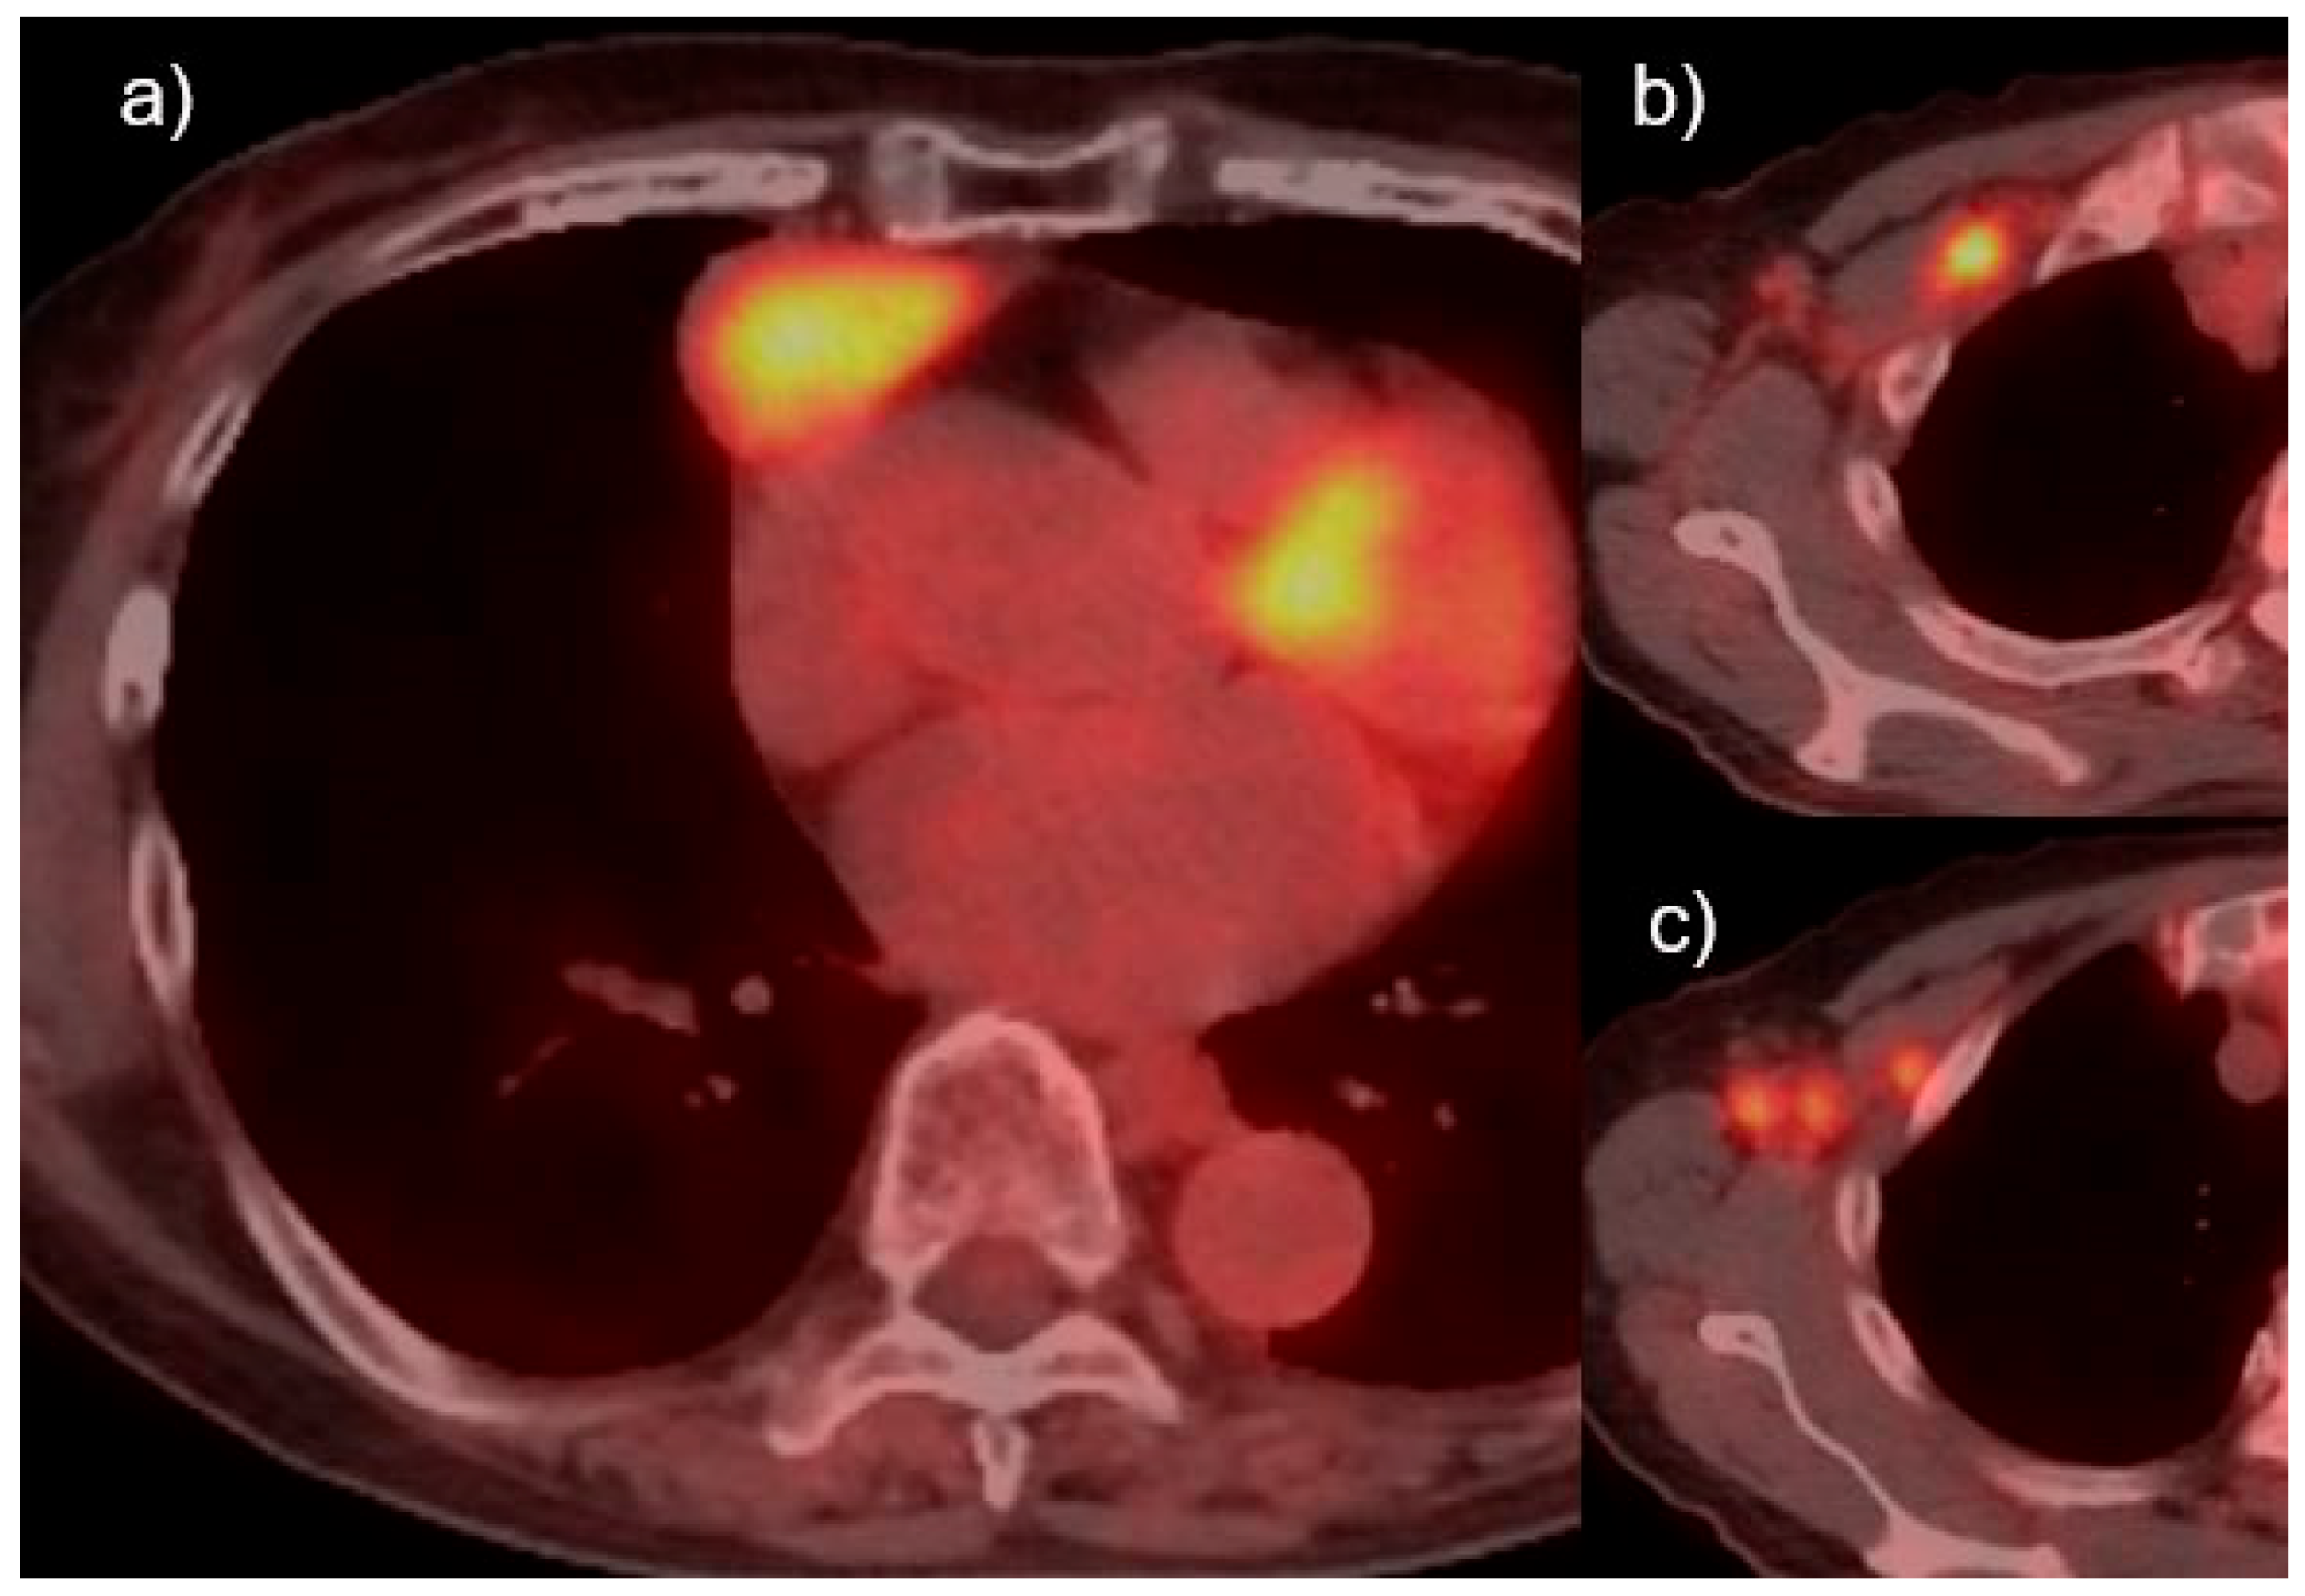

- Koppula, B.R.; Pipavath, S.; Lewis, D.H. Epstein-Barr Virus (EBV) Associated Lymphoepithelioma-Like Thymic Carcinoma Associated with Paraneoplastic Syndrome of Polymyositis: A rare tumor with rare association. Clin. Nucl. Med. 2009, 34, 686–688. [Google Scholar] [CrossRef]